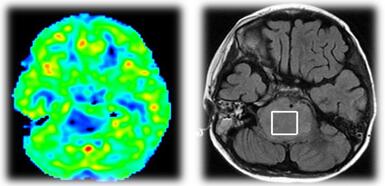

2016年5月27日,患儿急诊入我院肿瘤综合治疗中心。查MRI:脑干占位性病变,桥脑明显肿胀。ASL:脑干病变内明显低灌注,周围呈等灌注。MRS:Cho峰升高,NAA峰明显减低,Cho/Cr比值1.55,支持肿瘤性病变。